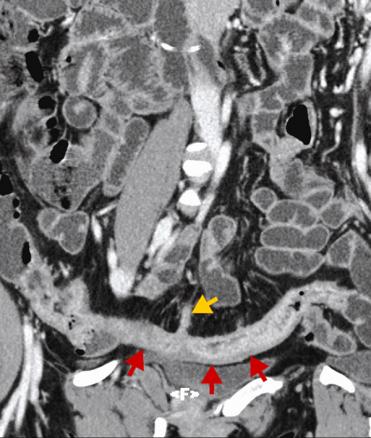

Entéroscanner avec ingestion de mannitol et injection de produit de constrate iodé. Reconstruction curviligne montrant une atteinte inflammatoire de la dernière anse (flèches rouges) avec fistule (flèche jaune) sur le bord mésentérique de l'anse.